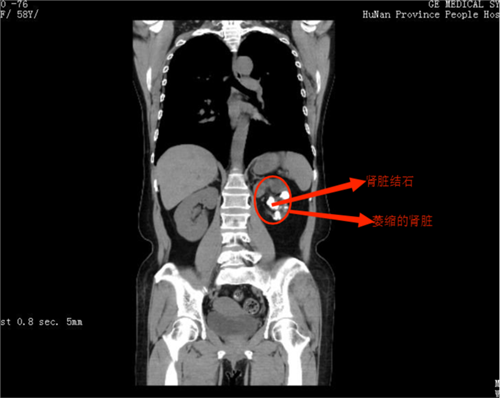

检查结果显示唐女士左肾满是结石,并且已经萎缩

入院后,杨科主任发现,唐女士为左肾多发铸型结石,结石长满整个肾脏,大的结石约3×4cm,左肾萎缩,肾显像结果显示其左肾肾功能几乎完全丧失。考虑结石如果不及时处理,会反复感染,长期刺激可能导致癌变,由于结石无法通过一次手术清除干净,且肾脏几乎没有功能,保肾取石没有意义。经过与唐女士及家人充分沟通,杨科主任团队为唐女士实施了左肾切除手术,手术顺利,经过恢复,唐女士于3月1日出院。